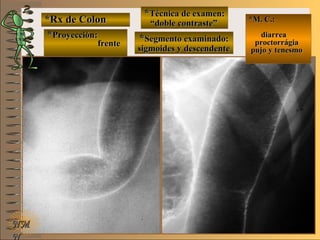

*Rx de Estómago*Rx de Estómago

**Proyección:Proyección:

**Técnica de examen:Técnica de examen:

A-A-

B-B-

C-C-